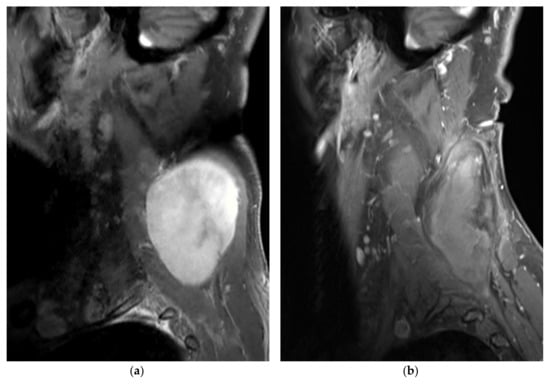

CA was generally performed using a double 10-min freeze protocol (two freezing cycles separated by a 9-min thawing cycle: 8-min passive + 1-min active). Intermittent CT controls during the freezing cycles were used to monitor ice ball extension (Figure 1). Duty cycle percentage (percentage on-off time, between 0 and 100%) and freezing cycle duration were adapted in cases of the ice ball approaching (<5 mm distance) a critical surrounding structure. Final CT images were obtained after cryoprobe retrieval to exclude any immediate complications, such as hematoma formation.

A 66-year-old male patient with extra-abdominal desmoid (EAD) tumor of the neck/cervical spine treated with percutaneous cryoablation (CA) (patient no. 4). (a,b) Sagittal gadolinium-enhanced fat-suppressed T1-weighted MR images prior to and 6 months after CA treatment, respectively. The desmoid tumor (DT) is well-delineated and homogeneously enhanced before CA. Six months after treatment, the DT has shrunk, and no residual tumor enhancement is seen; (c,d) Sagittal-reformatted CT images show several cryoprobes (19 in total) placed within the DT with the ice-ball (hypodense region) formation visible at the end of the second freezing cycle.